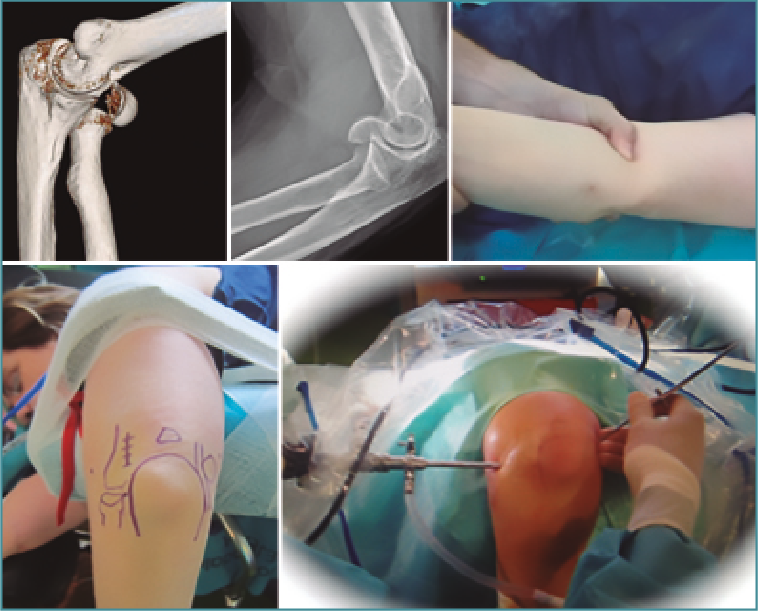

El uso del artroscopio como complemento para el tratamiento de las fracturas articulares –rodilla y muñeca especialmente– es una práctica generalizada en muchos servicios de traumatología, pero en la actualidad su uso sigue siendo infrecuente para las fracturas del área del codo (Figura 1).

Figura 1. Fractura de codo asistida por artroscopia.

Entendemos que para realizar esta técnica es esencial una adecuada formación y entrenamiento, dada su compleja curva de aprendizaje. En nuestro caso, realizamos una rotación médica en la Clínica Mayo con el Dr. Shawn O'Driscoll y, posteriormente, con el Dr. Hausman (Mount Sinai, New York). Ambos son probablemente de los cirujanos que más experiencia tienen en esta área a nivel mundial.

Nuestro objetivo es presentar las indicaciones de la artroscopia en el tratamiento de la lesiones articulares agudas del codo, así como sus complicaciones potenciales, argumentando que esta debe ser una ayuda complementaria (asistencia), no dudando en abrir el foco de fractura en casos de imposibilidad de reducción anatómica o fijación inestable. Igualmente, mostramos las posibles complicaciones y hacemos una puesta al día sobre la bibliografía que hay al respecto sobre este tema.

Nuestra experiencia durante el periodo 2007-2017 es de 110 artroscopias de codo, realizadas en distintos centros sanitarios (sanidad pública y privada). Si bien algunas indicaciones han sido las clásicas (extracción de cuerpos libres, epicondilalgias, artrolisis, valoración de osteocondritis disecante, biopsia sinovial y sinovectomía, así como el diagnóstico de condromatosis sinovial), desde hace años valoramos la inestimable ayuda del artroscopio para las fracturas articulares de esta compleja articulación (Figura 1).